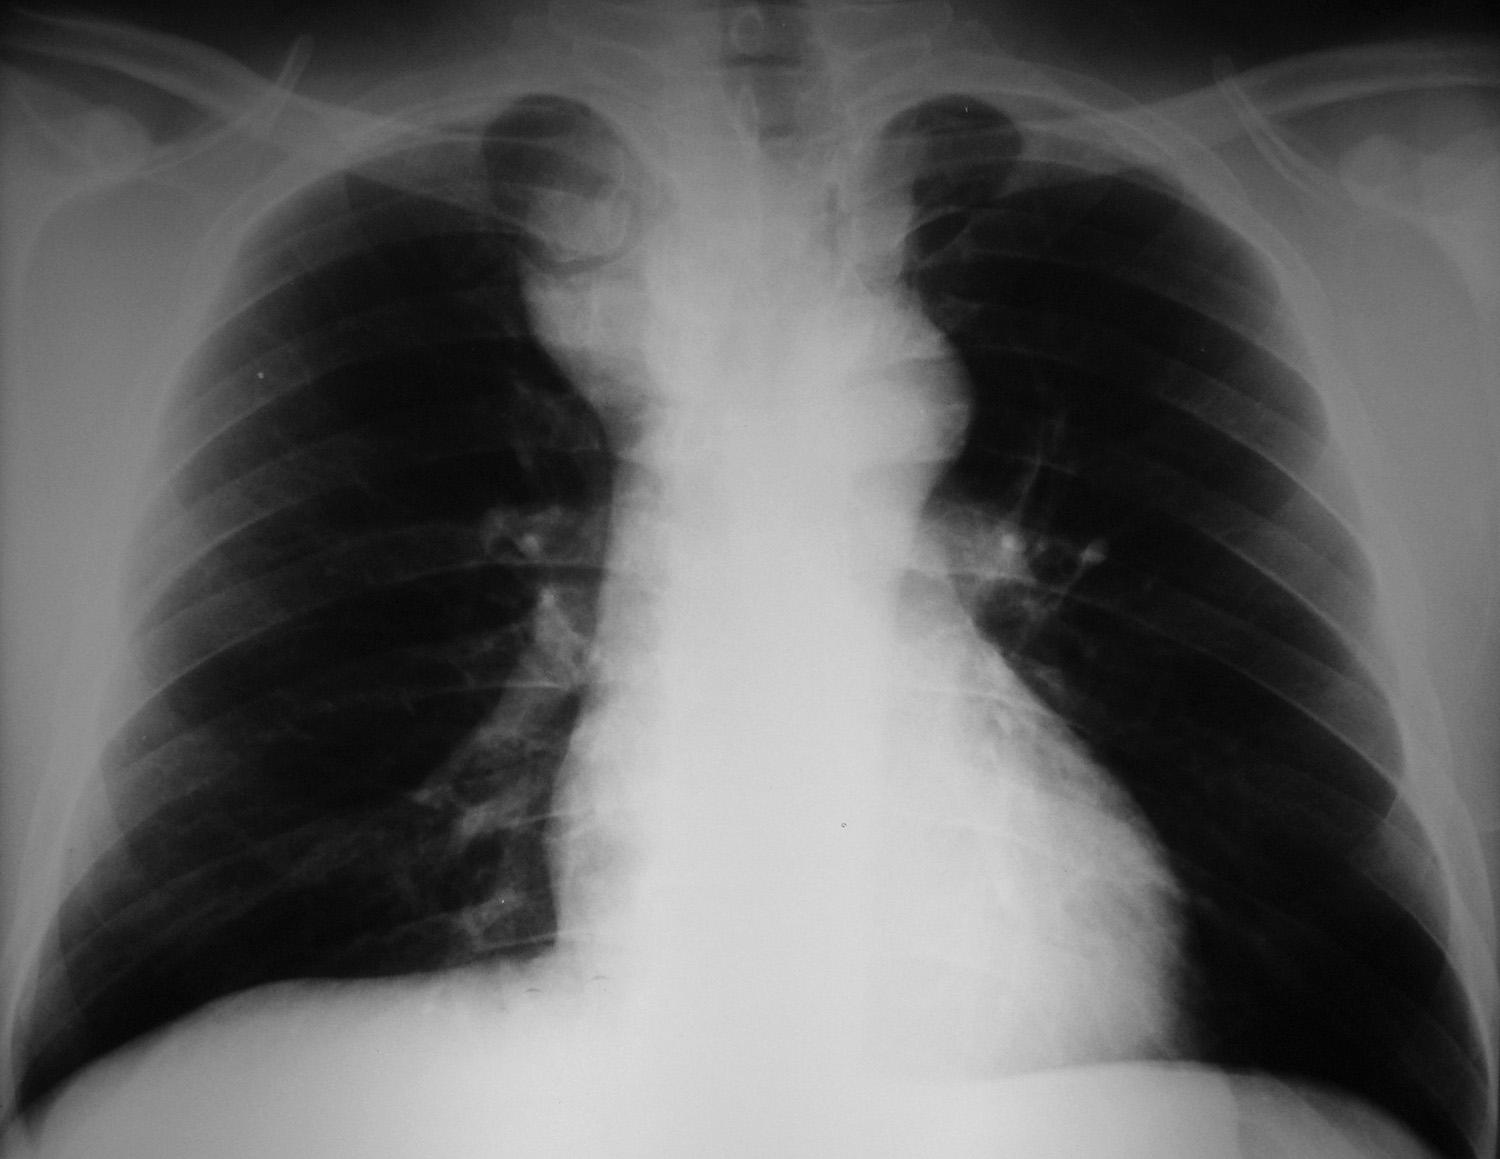

Tireóide ectópica mediastinal

Ectopic Mediastinal Thyroid

Tireóide ectópica mediastinal - Rx de torax com alargamento do mediastino.